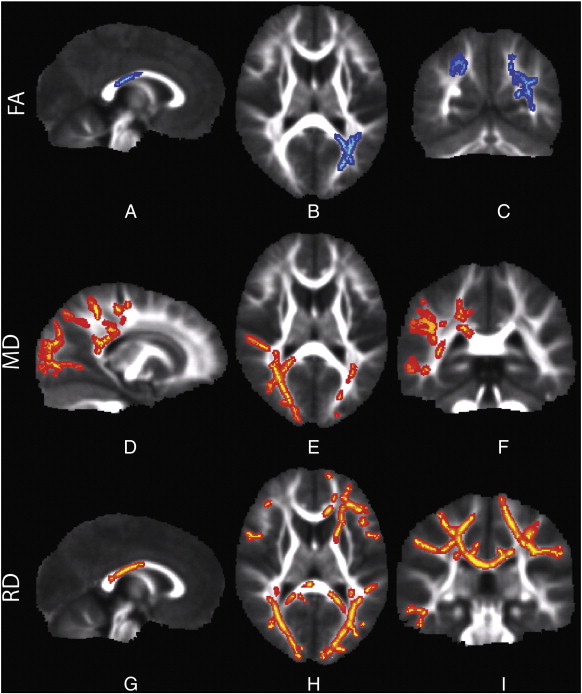

A recent study by investigators from the University of California, San Francisco demonstrated quantifiable differences in brain structure among kids with sensory processing disorder, indicating a biological basis for the condition that sets it apart from other neurodevelopmental disorders.